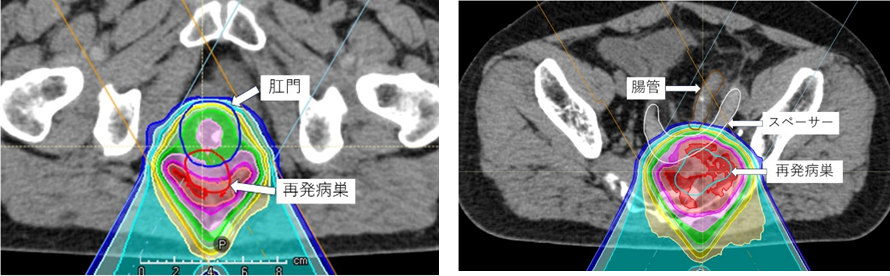

照射回数は病巣の部位や大きさにより変わりますが、基本は35回(7週間)です。可能な範囲で抗がん剤を併用します。腸管や膀胱などの正常臓器への照射線量を安全域まで下げて再発病巣に照射します。正常臓器を温存しつつ再発病巣に高線量を投与するためにスペーサーを留置する可能性があります。

スキャニング照射により正常臓器への線量を可能な限り低下することが可能です。これにより副作用を極力抑えることができます。下図左はスキャニング照射技術により肛門への線量を抑えつつ再発病巣に高線量を投与した症例の線量分布図です。経験豊富な施設との医療連携によりスペーサー留置を安全かつスムーズに行うことができます。下図右はスペーサー留置により腸管への線量を抑えつつ再発病巣に高線量を投与した症例の線量分布図です。骨軟部腫瘍のページでもスペーサー留置症例に関して紹介していますので、ご参照ください。